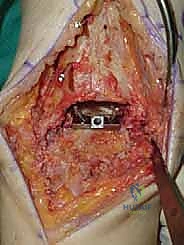

4. وضع أدلة القطع (Jig Placement and Alignment)

تعتمد دقة الجراحة على المحاذاة الصحيحة. يتم استخدام أجهزة توجيه متطورة (Jigs) تثبت على عظمة الساق باستخدام دبابيس معدنية. يتم التحقق من صحة الزوايا والمحاور باستخدام جهاز الأشعة السينية المباشر داخل غرفة العمليات (C-arm Fluoroscopy). يضمن الدكتور هطيف أن يكون القطع موازياً للأرض تماماً عند وقوف المريض.

5. القطع العظمي الظنبوبي (Tibial Bone Cut)

باستخدام منشار جراحي دقيق التذبذب، يتم إزالة شريحة رقيقة جداً (بضعة مليمترات) من السطح السفلي التالف لعظمة الظنبوب. يتم القطع بحذر شديد لتجنب إصابة الأوتار الخلفية أو الأوعية الدموية.

6. القطع العظمي الكاحلي (Talar Bone Cut)